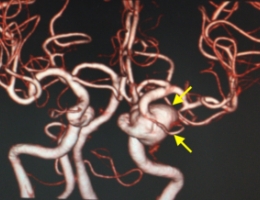

治療後

物が二重に見えるようになって発症した内頚動脈大型動脈瘤(矢印)の症例です。クリッピング術で直接動脈瘤をつぶすことができないため、バイパス術(矢印)を増設し内頚動脈を遮断することで動脈瘤を治療しました。